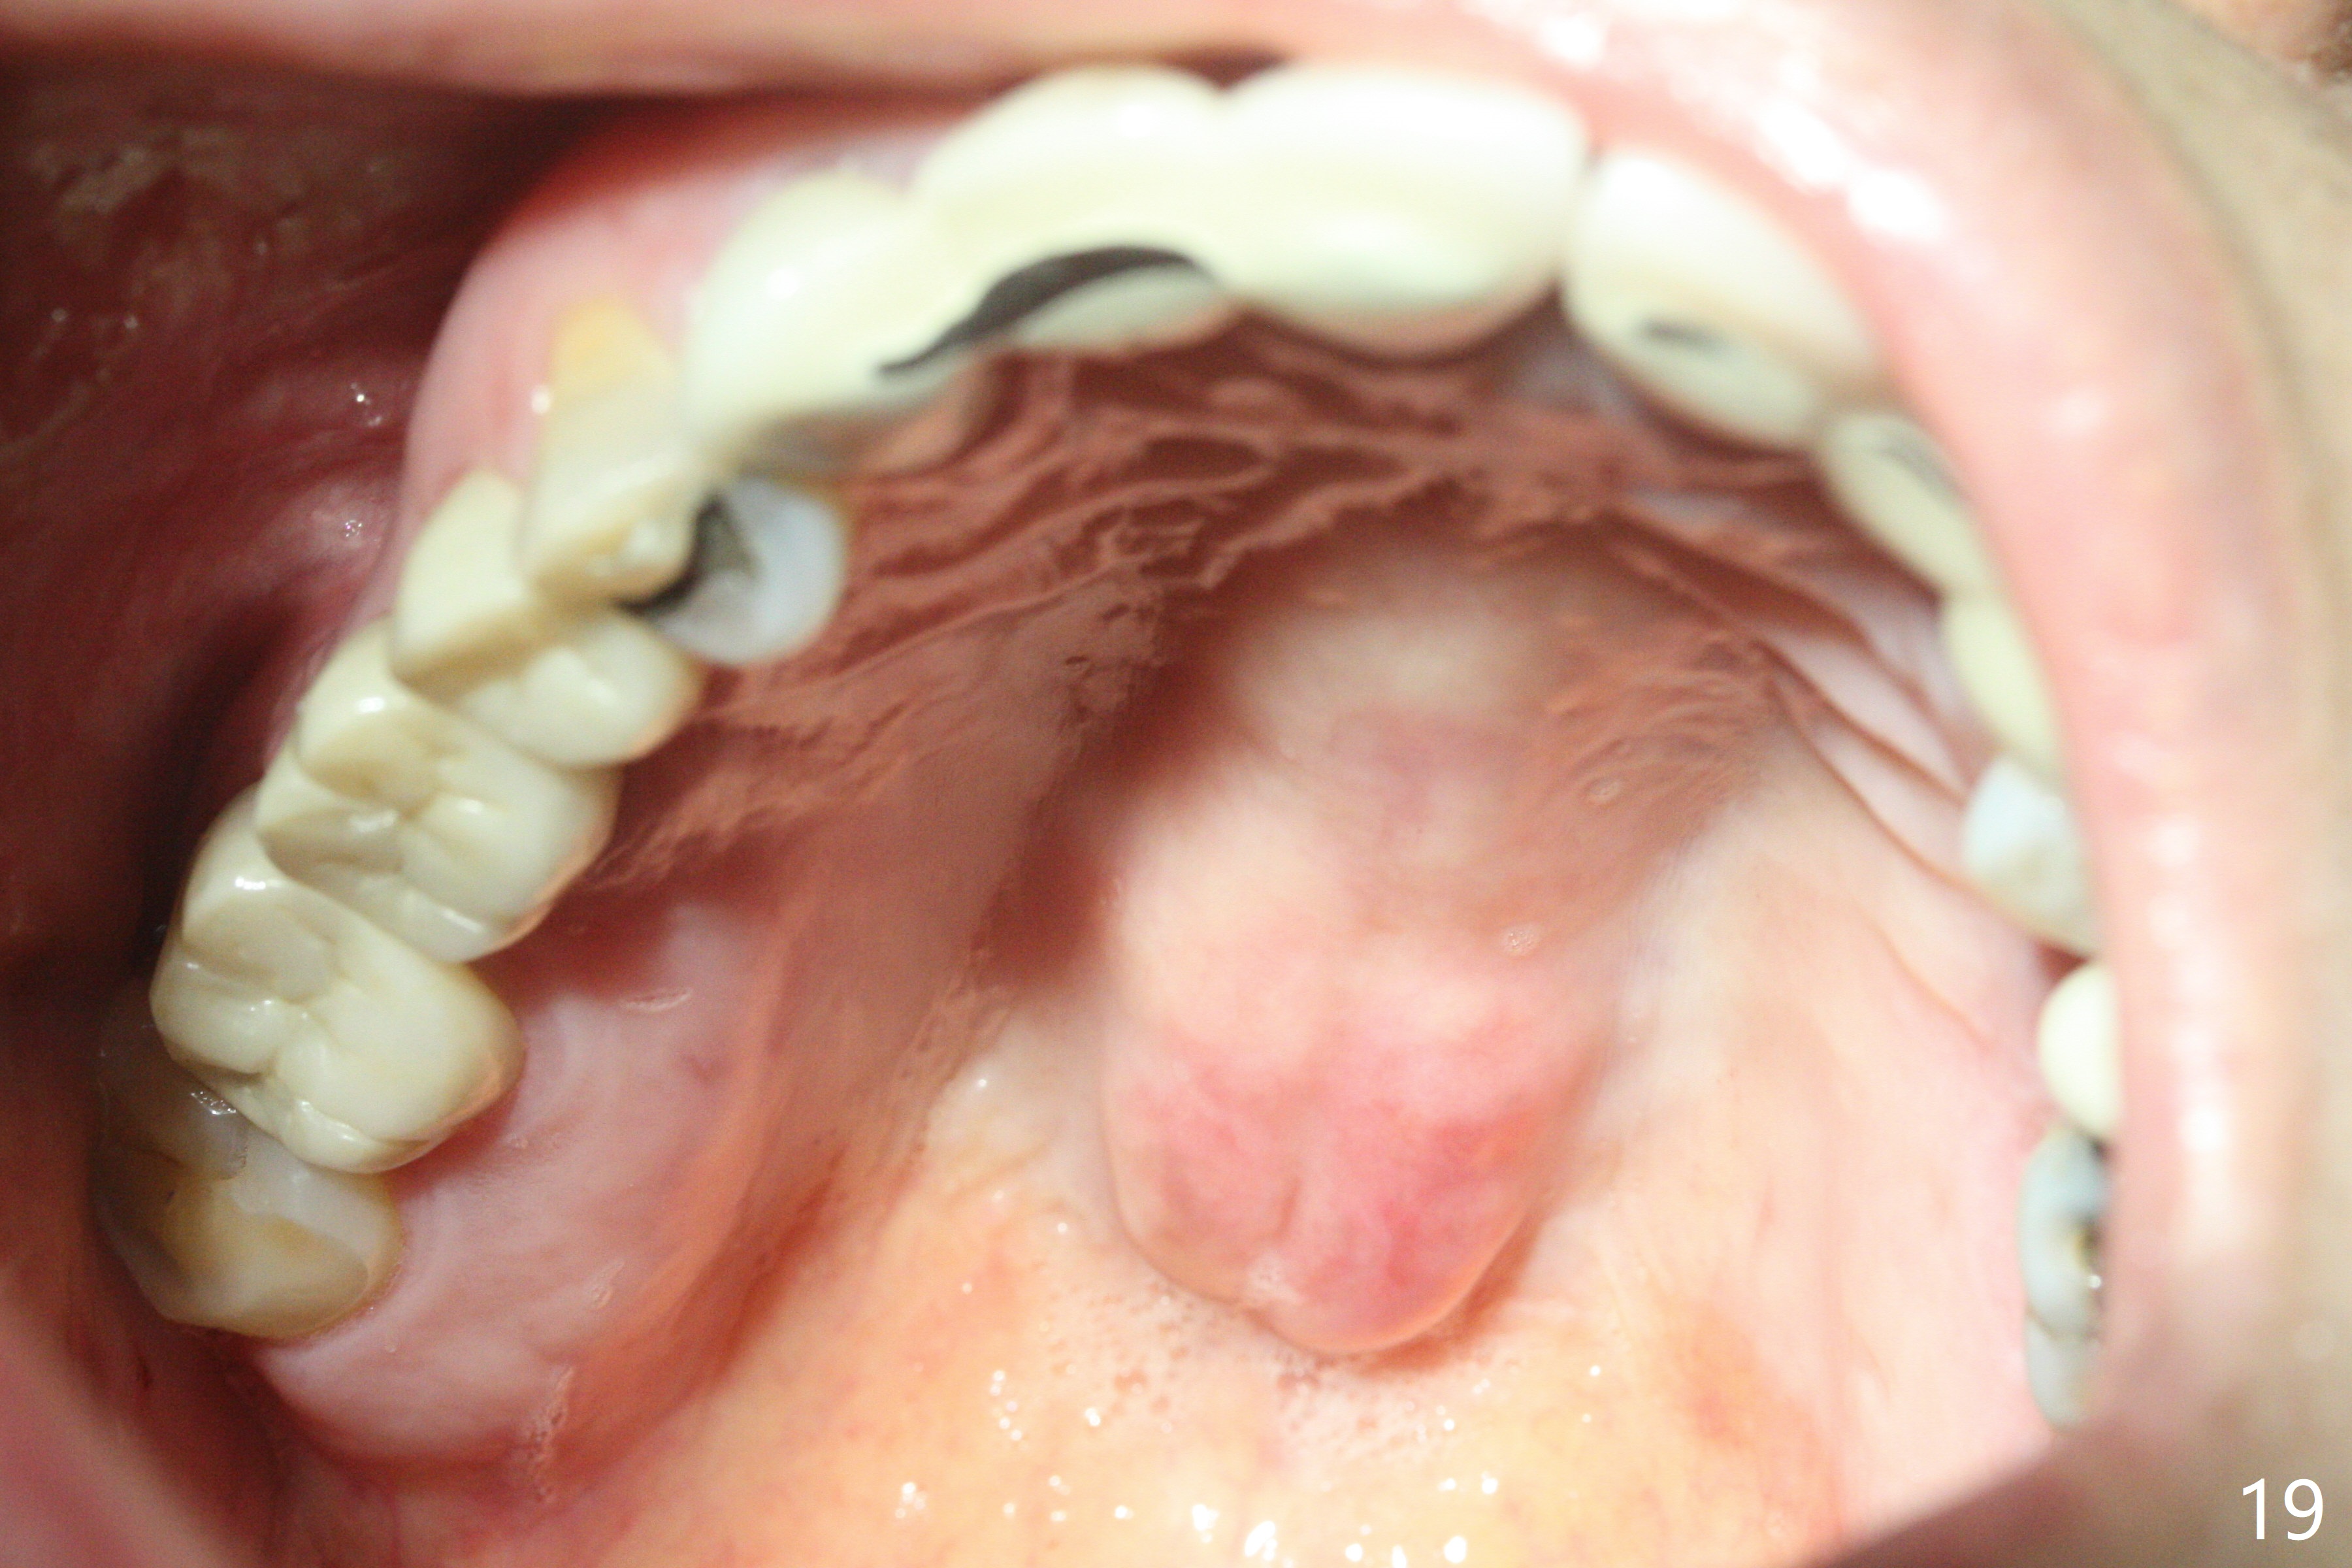

In brief, bone expanders or osteotomes can be used for bone expansion and condensation to improve primary stability of implant placement. No bone graft appears to be needed. The buccal concavity remains minimal 6 years post cementation (Fig.18). In fact he is a bruxer with torus palatinus (Fig.19). The bridge of #9-11 is loose because of subgingival fracture of the abutment of #11 for 2.5 years (Fig.20).